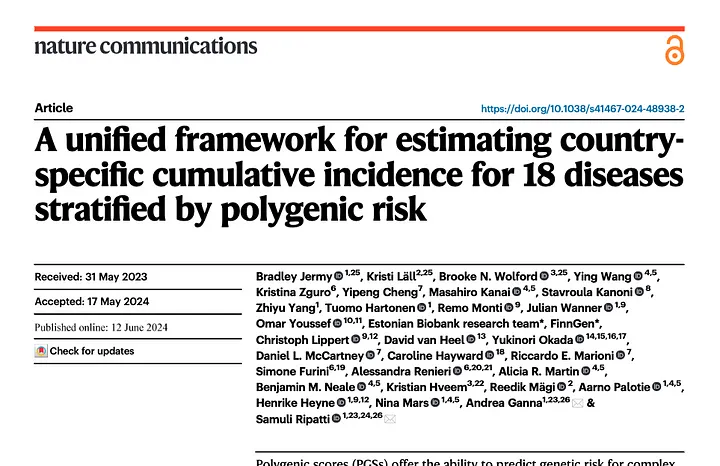

Nature Communications